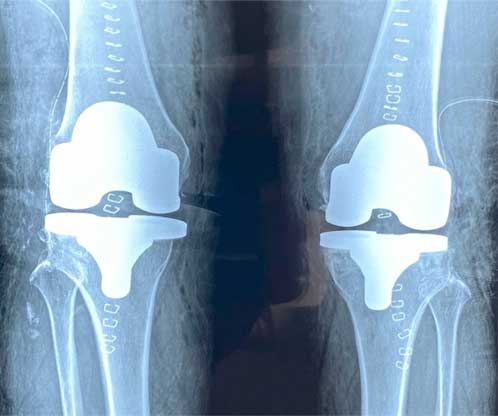

También conocida como artroplastia de rodilla, es la sustitución artificial de la articulación desgastada por artrosis con un implante de metal y polietileno que ayuda a aliviar el dolor y restaurar la función.

La razón más frecuente es aliviar el dolor intenso causado por artrosis, corregir las deformidades angulares en varo, valgo y contractura en flexión en adultos mayores y para adultos jóvenes, está indicada en lesiones crónicas articulares que ocasionan un desgaste acelerado.

El paciente puede caminar desde el mismo día de la cirugía, se da de alta a su domicilio a las 24 horas, realiza actividades cotidianas en casa de forma autónoma desde la primera semana, recupera el 80% de la función de la rodilla al primer mes, 90% de la función en el segundo mes y 92% - 98% de la función en el tercer mes.

Eliminar el dolor en la zona afectada, mejorar la función como es fuerza muscular, movimiento, estabilidad, biomecánica, logrando mejorar la calidad de vida del paciente.